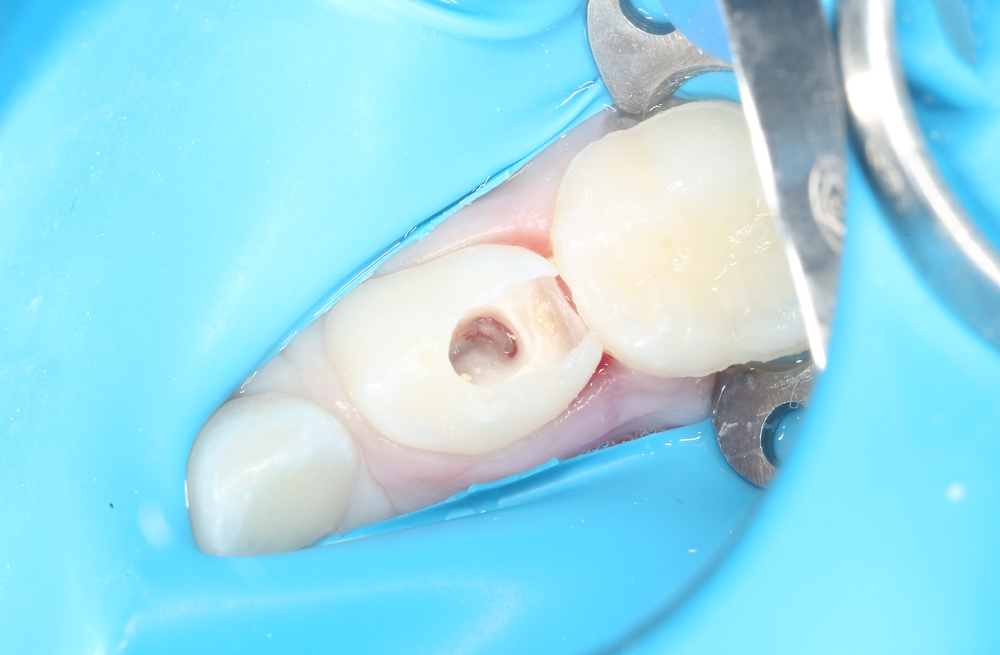

Пломбирование кариозного дефекта коренного зуба с сохранением здоровых тканей

Диагностика и лечение скрытого кариеса на постоянном зубе у семилетнего ребёнка

Своевременное лечение кариеса постоянного зуба у подростка без жалоб

Лечение кариеса на жевательной поверхности постоянного зуба у подростка

Восстановление жевательного зуба композитной пломбой с учётом анатомии и цвета эмали

Композитная реставрация зуба при среднем кариесе у ребёнка школьного возраста

Удаление среднего кариеса с пломбированием зуба композитным материалом

Восстановление жевательной поверхности постоянного зуба после кариозного разрушения у подростка

Эстетическая реставрация постоянного зуба при кариесе дентина

Восстановление зуба подростку при кариесе дентина пломбировочным материалом Harmonize A2

Пломбирование зубов подростку с использованием композита Harmonize A2

Лечение кариеса жевательного зуба ребенку 11 лет

Лечение среднего кариеса подростку 14 лет с применением пломбировочного материала Гармонайз

Лечение среднего кариеса постоянного зуба ребенку 8 лет